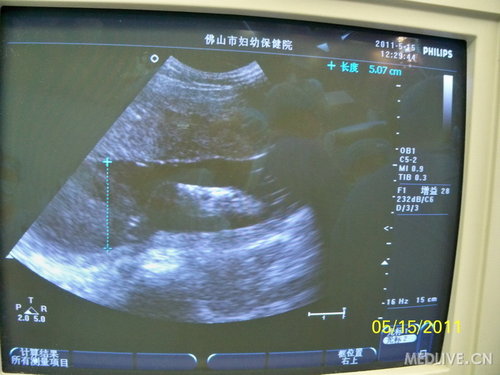

B超监护下的胎儿心率、羊水深度

http://webres.medlive.cn/upload/000/016/713

术毕B超确定胎心音在正常范围。

http://webres.medlive.cn/upload/000/016/719

清点敷料器械无误,检查监测胎心145次/分,经皮血氧饱和度70%,胎儿肤色红润、温暖。取下左侧肢体监护探头,将左侧肢体放回宫腔。外科胎儿手术完毕,术程顺利,术中胎心及血氧饱和度平稳无波动,术中出血约4ml。术后标本送病理检查。产科继续行子宫缝合,大网膜覆盖子宫切口及关腹。术后监测胎心148次/分,超声羊水监测最大厚度约5.38cm,胎儿心脏向左侧部分复位。